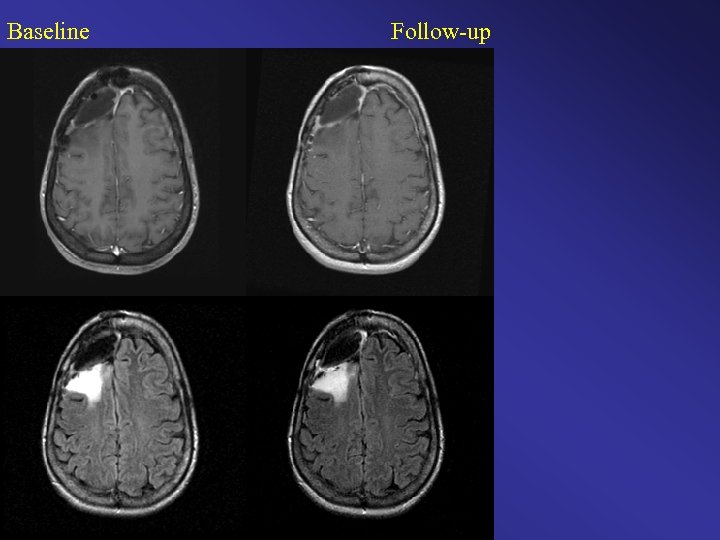

Baseline Follow-up

Baseline Follow-up Color Change Map Original Clinical Interpretation: Stable / Time to Progression Diagnosis > 18 months